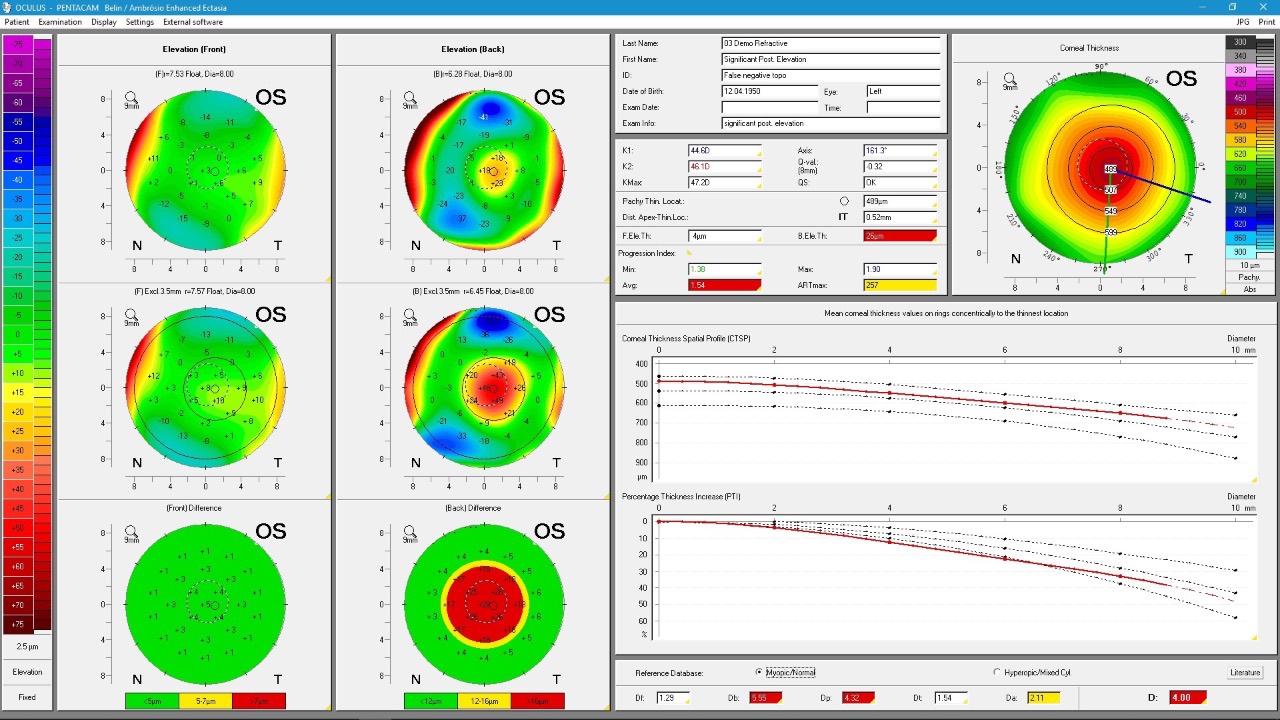

Snoring & Keratoconus

Is there really a connection?

A bidirectional Mendelian randomization study has found interesting evidence supporting the role of snoring in keratoconus (KCN). This was uncovered utilizing genetic variations with analyzed data from over 400,000 participants.

The results revealed a causal effect ...